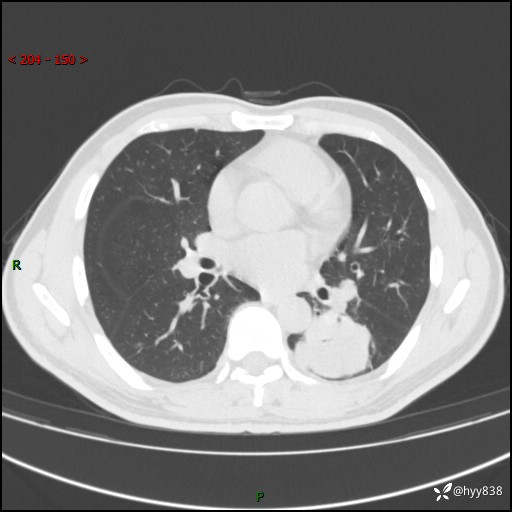

57岁/男,间断痰中带血1月余。纤支镜没有取到东西,穿刺轻松搞定---结果公布~

现病史:患者1月余前无明显诱因出现咯血症状,为痰中带血,量不大,伴轻度咳嗽,2024-3-26于当地市中医医院行胸部CT示:左肺下叶占位性病变。现患者仍有咳嗽不适,无发热乏力,无腹泻、便秘,无咳嗽,无头晕、无双下肢水肿等伴随症状,未行特殊治疗,今日患者再次出现咯血症状。患者为求进一步诊治,遂入我院,门诊以“肺脓肿”收入我科。 患者病程中,精神食欲可,二便正常,体力体重较前变化不明显。

胸部CT平扫